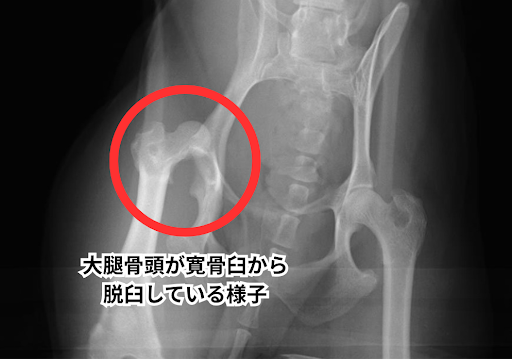

手術前のレントゲンでは股関節脱臼が明確にわかります。

股関節は骨盤のくぼみ(寛骨臼:かんこつきゅう)に、太ももの骨の先端(大腿骨頭:だいたいこっとう)がはまり込むことで形成されています。

この大腿骨頭が寛骨臼から外れてしまった状態を股関節脱臼と呼びます。